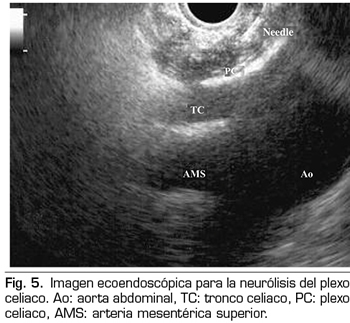

La ecoendoscopia ofrece la ventaja de una mayor visualización del plexo celiaco a corta proximidad, permitiendo una mayor precisión y seguridad en la administración del agente neurolítico y evitando la inyección en estructuras vasculares mediante el uso del Doppler (37) (Figura 5). No obstante, los trabajos que apoyan la neurólisis ecoendoscópica, considerada al igual que la técnica percutánea como una terapia de rescate, están limitados a estudios retrospectivos no controlados (38). Pauli y cols. publicaron un metanálisis que concluye que esta técnica consigue una reducción del dolor del 80 % en pacientes con cáncer de páncreas (39). Algunos estudios muestran un ligero descenso en el consumo de opioides, pero sin una fuerte evidencia científica.